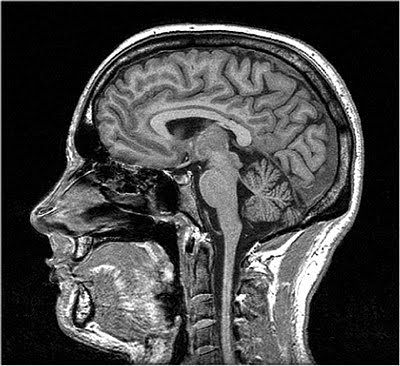

[Picture]

Magnetic Resonance Imaging (MRI).

Takes advantage of the magnetic properties of hydrogen, specifically protons in the hydrogen atom.

Used for structural images of the brain.

Excellent spatial resolution.

MRIs can help measure gray matter volume, thickness, and shape, and abnormalities have been documented with some of the most common mental health disorders like depression, ADHD, and anxiety.